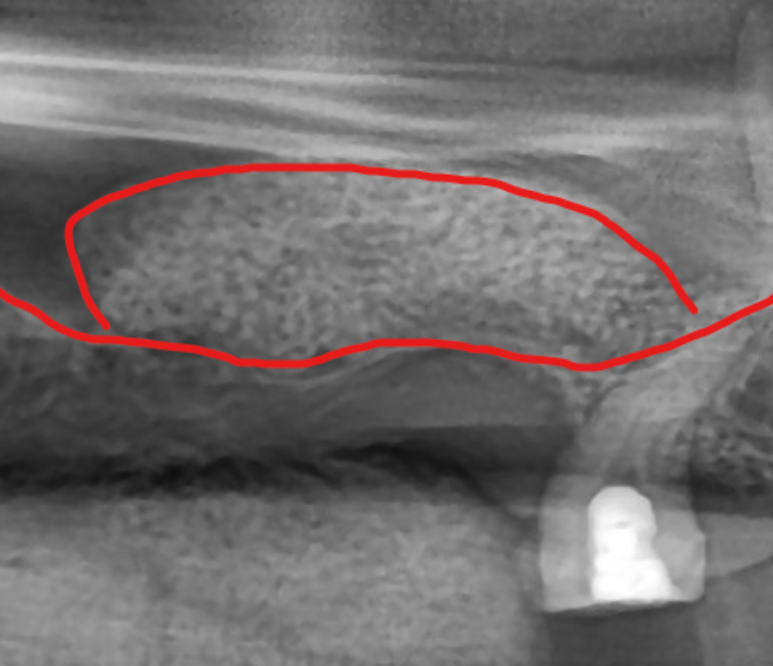

광대뼈 안쪽에는 상악동이라고 불리는

빈 공기 주머니가 존재합니다.

이 주머니는 코와 연결되어 공기가 드나드는

역할을 하는데, 치아가 빠지고 시간이 지나면

잇몸 뼈는 점차 흡수되어 얇아지고,

위에 있던 공기 주머니는 아래로 처져 내려오게 됩니다.

결국 임플란트를 심어야 할 잇몸 뼈의 두께가

종잇장처럼 얇아져 식립이 불가능한 상태가 됩니다.

이때 내려온 공기 주머니의 얇은 막을

위로 조심스럽게 들어 올리고,

그 빈 공간에 뼈 이식재를 채워 임플란트를 심을 수

있는 충분한 높이를 확보하는 과정이 필요합니다.

뼈가 하얗게 채워진 모습

이를 상악동 거상술이라고 부르며,

임플란트의 성공적인 식립을 위한 과정입니다.